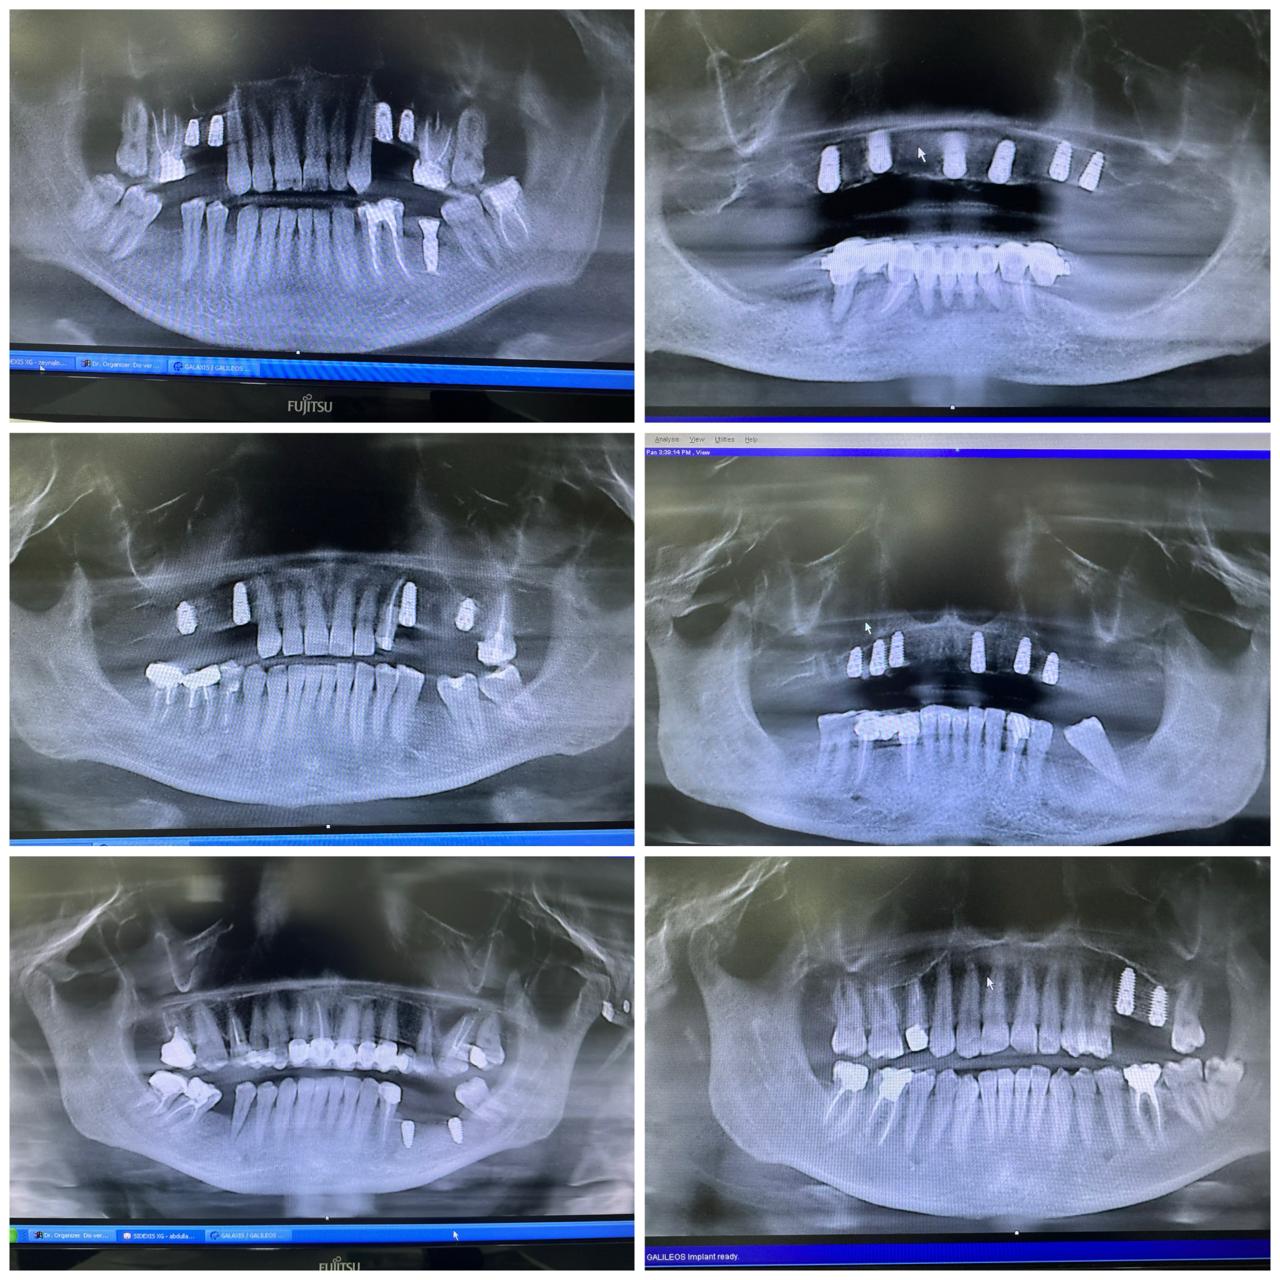

İmplant rentgenləri

Sinus lifting